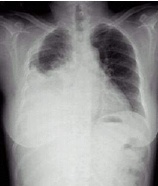

病史:女性,76岁,胸闷伴呼吸困难6天,不能平卧1天。诊断:

○右侧胸腔积液

○右下肺不张

○右下胸膜肥厚

○大叶肺炎

气胸